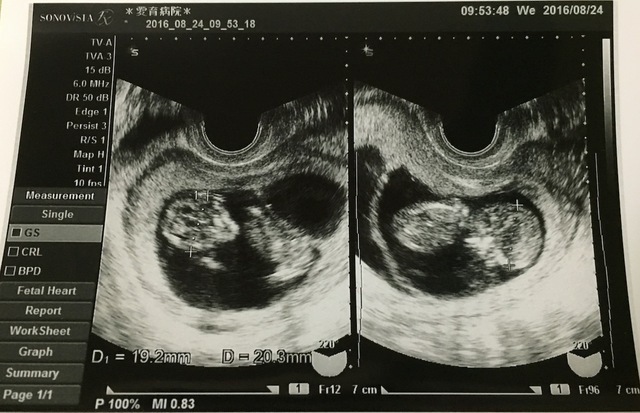

15週6日(15w6d・男の子・双子)|maiiii さん(17歳)

エコー写真撮影時のエピソード:

初めての妊娠。産婦人科に行くと双子ですと言われ、義母さんは信じられないと、もう一回検診しに行きました。やっぱり双子。親戚に双子は居なくてみんな驚きました。

産んでいいって言われてこれからの話し合いをして、毎回の検診には義母さんがついてきてくれました。双子は管理入院もなく、2人とも2キロ越えで立派に生まれてきました。